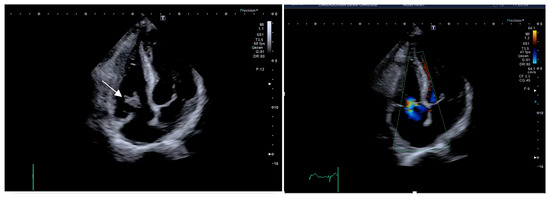

2.3. Case 3